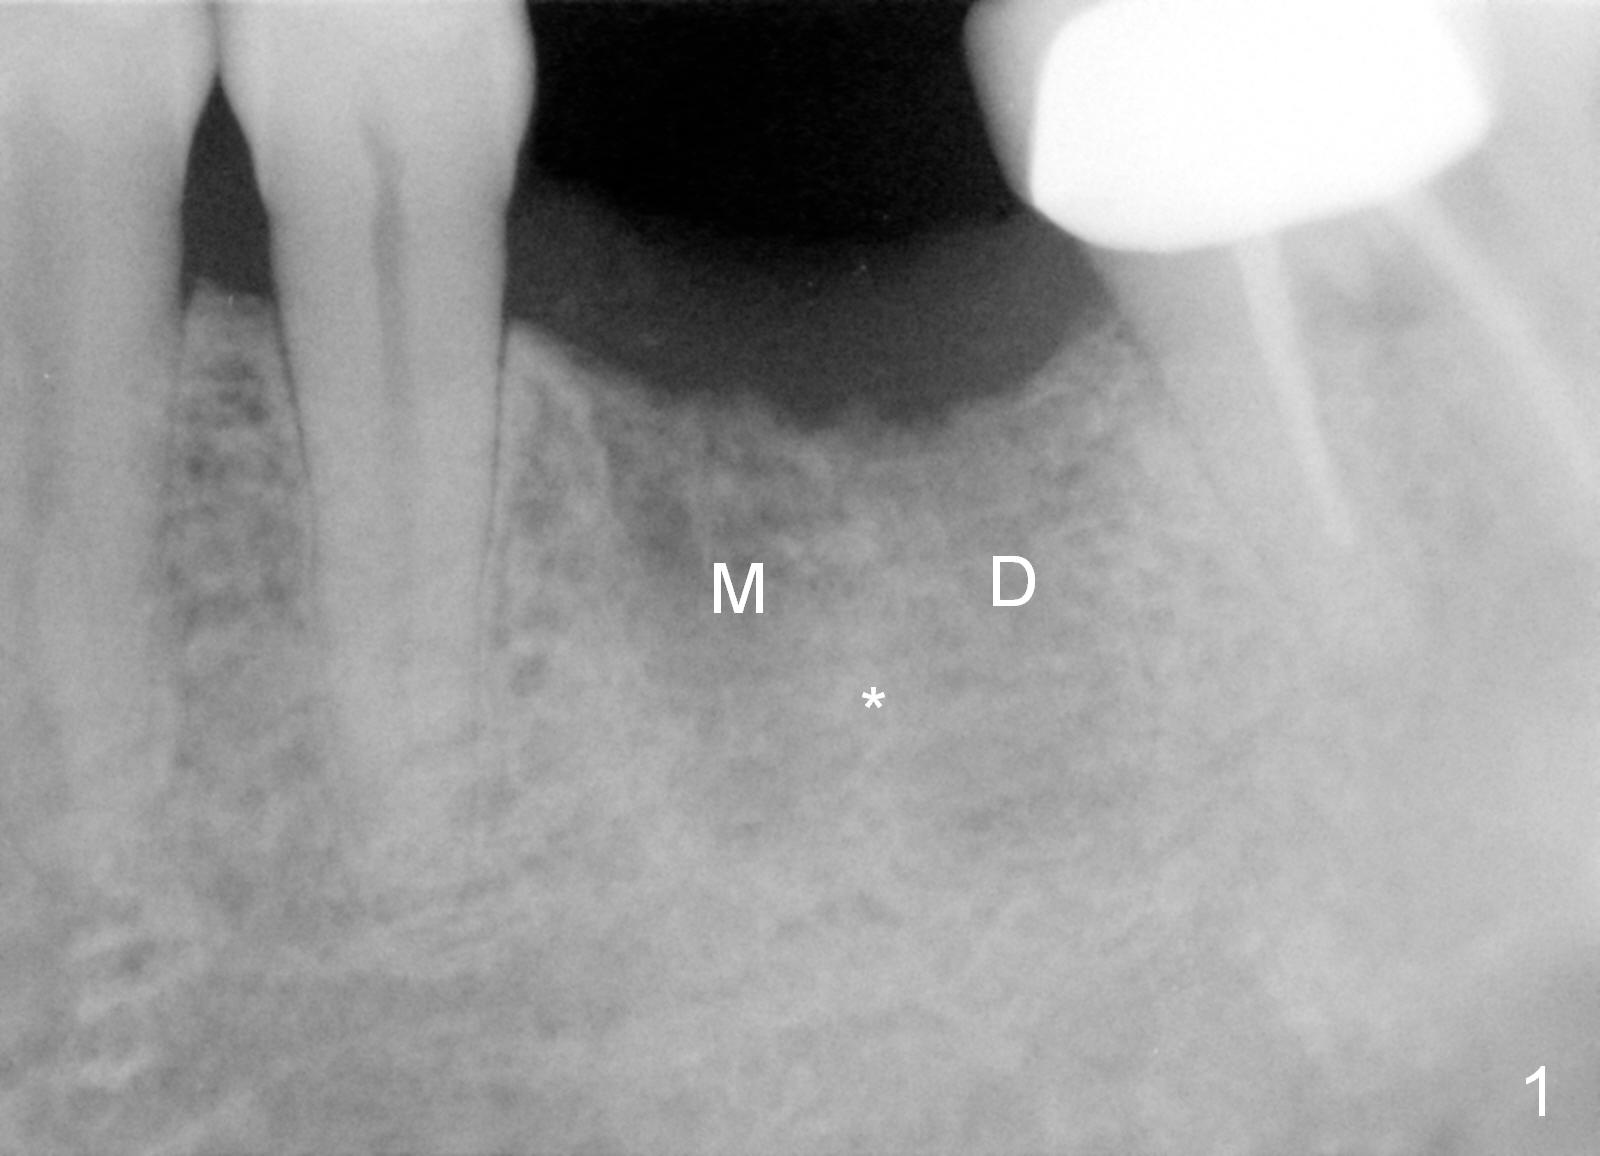

A 68-year-old man had the tooth #19 extracted more than 6 months ago (Fig.1). When his wife has had an immediate implant placed, he decides to have his implant placed. After incision, use the 5 mm implant positioner to check the width of the crestal bone. If it is less than 6 mm, the implant length will be most likely 14 mm. Clinical exam has revealed moderate ridge atrophy. Anyway, the initial osteotomy is 12 mm. It should pass the apices of the mesial (M) and distal (D) sockets (Fig.2 ^) in the middle of the septum (as compared to Fig.1 S). If there is enough safety margin, the osteotomy depth will be set at 14 mm (Fig.3 (red dashed line: the superior border of the Inferior Alveolar Canal)). There is no indication for intraop localized use of antibiotic.